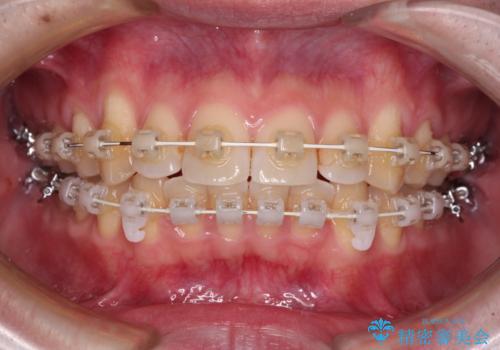

- 矯正装置

- 審美装置

- 上下前歯のデコボコを気にして来院された患者様です。

マウスピース矯正でもワイヤー矯正でも対応可能でしたが、インビザラインによる自己管理が煩わしいとのことで、ワイヤー装置にて矯正治療を行うこととしました。